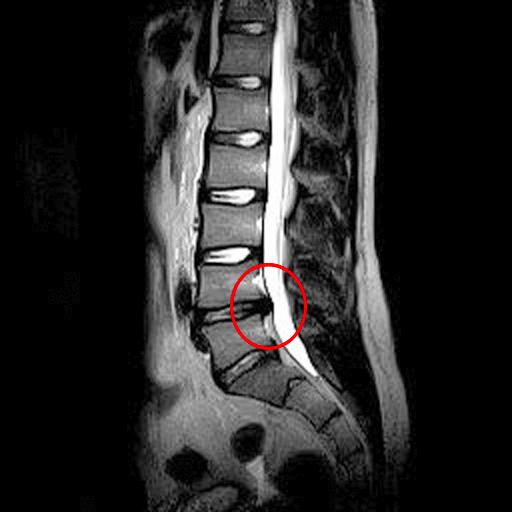

Herniated Disc Mri L5 S1 Lumbar Herniated Disc A More in Depth Look Hernia Lumbar L5 Lumbar disc herniation is a very common cause of low back pain and unilateral leg pain, known as radiculopathy. What is a herniated disk? In rare cases a large disc herniation can lead. In most cases of herniated disk, a physical exam and a medical history are all that are needed for a diagnosis. A herniated disk is a condition. Hernia Lumbar L5.

Herniation Del Disco, Espina Dorsal Lumbar MRI Imagen de archivo Hernia Lumbar L5 Lumbar disc herniation is a very common cause of low back pain and unilateral leg pain, known as radiculopathy. A herniated disk is a condition that can occur anywhere along the spine, but most often occurs in the lower back. In most cases of herniated disk, a physical exam and a medical history are all that are needed for a. Hernia Lumbar L5.

Lumbar Disc Herniation (a) Showing herniated disc at L4/L5 level [14 Hernia Lumbar L5 Alleviate pain and other symptoms such as numbness. A herniated disk is an injury of the spine (backbone). It is one of the. You have a series of bones (vertebrae) in your spine,. In most cases of herniated disk, a physical exam and a medical history are all that are needed for a diagnosis. In rare cases a large disc. Hernia Lumbar L5.

RM HERNIA DISCAL LUMBAR Blog de Fisioterapia Hernia Lumbar L5 In rare cases a large disc herniation can lead. You have a series of bones (vertebrae) in your spine,. In most cases of herniated disk, a physical exam and a medical history are all that are needed for a diagnosis. Lumbar disc herniation is a very common cause of low back pain and unilateral leg pain, known as radiculopathy. It. Hernia Lumbar L5.

Como se ve una hernia discal en una resonancia.Hernia discal L5S1 Hernia Lumbar L5 In most cases of herniated disk, a physical exam and a medical history are all that are needed for a diagnosis. You have a series of bones (vertebrae) in your spine,. In rare cases a large disc herniation can lead. A herniated disk is a condition that can occur anywhere along the spine, but most often occurs in the lower. Hernia Lumbar L5.